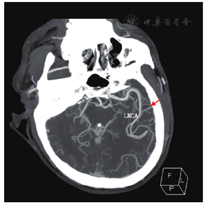

患者男性,57岁,因"胸闷、气短5年,再发加重一周"于2019年4月29日入院。患者5年前(2014年)开始出现胸闷、气短不适,体力活动较前稍有下降,当地医院诊断为"扩张型心肌病",给予对症处理后症状好转,长期口服培哚普利、螺内酯、琥珀酸美托洛尔缓释片。2016年症状再发,当地医院行超声心动图检查:左心室舒张末期内径(left ventricular end-diastolic diameter, LVEDD)63 mm,左心室射血分数(left ventricular ejection fraction, LVEF)44%。冠状动脉造影示:冠状动脉硬化,继续药物治疗,未规律复查。一周前患者感冒后咳嗽、咳痰,胸闷、气短逐渐加重,稍重体力活动即感胸闷,夜间可平卧入睡,偶有阵发性呼吸困难,双下肢无水肿,为进一步诊治就诊我院门诊,门诊以"扩张型心肌病"收治入院。既往发现血压高10年,最高150/120 mmHg(1 mmHg = 0.133 kPa),目前口服培哚普利,血压控制不详。入院体格检查:体温36.5 ℃,脉搏106次/min,呼吸频率21次/min,血压145/97 mmHg。神志清楚,颈软,颈静脉无怒张;双肺呼吸音清,双肺未闻及干湿性啰音;心界不大,心率106次/min,律不齐,可闻及早搏,约15次/min,各瓣膜听诊区未闻及杂音;腹平软,无压痛及反跳痛,肝脾肋下未及;双下肢无水肿,双侧足背动脉搏动对称、良好。辅助检查:血常规:中性粒细胞百分率52.90 %,白细胞计数、红细胞计数、血红蛋白水平、血小板计数均正常;凝血功能:凝血酶原时间17.4 s,活化部分凝血活酶时间(activated partial prothrombin time, APTT)25.9 s,凝血酶原时间国际标准化比值(international normalized ratio, INR)1.15;血生化:血钾4.42 mmol/L,血清肌酐99 μmol/L,肾小球滤过率73 mL/min,血清尿酸631 μmol/L;N末端B型利钠肽前体(N terminal pro-B type natriuretic peptide, NT-pro BNP)2430.00 pg/mL;心肌酶谱:心肌肌钙蛋白T 18 ng/L(参考范围0~14 ng/L);血浆D-二聚体0.34 mg/L。心电图:窦性心动过速,心率103次/min,QRS 142 ms,室内传导延迟,室性期前收缩(室早)。超声心动图:左心房前后径55 mm,右心房前后径52 mm,LVEDD 68 mm,LVEF 36%,左心扩大,右房扩大,室间隔、左室壁运动幅度普遍减低,二、三尖瓣轻-中度返流,肺动脉高压(轻度),左心收缩功能减低,心包少量积液。胸片:肺淤血,肺无实变,右膈光整,左侧胸腔少量积液。主动脉结宽,肺动脉段平,左心房、室增大。心胸比率:0.56。综上诊断:1.扩张型心肌病,心功能Ⅲ级(NYHA心功能分级);2.心律失常,室性期前收缩;3.高血压病3级(极高危)。患者入院后给予沙库巴曲缬沙坦、美托洛尔、呋塞米及螺内酯口服。患者入院后频繁发作室性期前收缩(室早),并发作室性心动过速(室速),给予静脉泵入尼非卡兰可转复为窦性心律,同时加用口服胺碘酮治疗室性心律失常,静脉24 h持续泵入左西孟旦改善心功能。入院第9天(2019年5月8日)行心脏磁共振成像检查(图1)示:LVEDD 71 mm,左心室收缩末期内径(left ventricular end-systolic diameter, LVESD)66 mm,LVEF 15%,右心室射血分数(right ventricular ejection fraction, RVEF)27%,左心室扩大,左心室收缩功能明显减低,右心室收缩功能减低,左心室血栓形成,大小分别为2.2 cm×1.2 cm及2.2 cm×0.7 cm,心肌灌注显像显示心肌未见明显缺血,心肌延迟显像显示室间隔及左室下壁基底段至中间段心肌中层纤维化形成。当日复查超声心动图示:LVEDD 71 mm,LVEF 28%,1、左心扩大,右心房扩大;2、左心室血栓形成(室间隔处可见稍高回声团附着,范围约5.3 cm×1.2 cm);3、室间隔、左室壁运动幅度普遍明显减低;4、二、三尖瓣轻度反流;5、肺动脉高压(轻度);6、左心收缩功能减低;7、心包少量积液。立即给予肝素抗凝治疗,APTT维持40~60s。患者入院后经规范药物治疗,心功能仍为Ⅲ~Ⅳ级,且存在频发室早,短阵室速,抗心律失常药物治疗效果不佳,猝死风险高,遂于入院后第10天(2019年5月9日)行心脏再同步治疗-除颤起搏器(cardiac resynchronization therapy-defibrillator, CRT-D)植入术,术后继续肝素抗凝治疗,术后第3天(2019年5月11日)患者突发失语,右侧肢体偏瘫,肌力0级,考虑急性脑血管意外,急诊行头颈部CTA检查(图2)示:左侧大脑中动脉起始部及以远闭塞,左侧大脑前动脉A2段以远闭塞可能。复查超声心动图提示未见心室血栓,考虑心室血栓脱落所致,神经内科急会诊后建议急诊取栓手术,于发病后约2小时行急诊取栓术,术后患者神志清楚、四肢肌力恢复正常,但仍失语。患者脑梗塞急性期,出血风险高,多次复查心脏彩超未见心室血栓,神经内科会诊建议低剂量抗凝预防血栓形成,术后给予利伐沙班片15 mg,1次/d,口服抗凝治疗,行血浆抗Xa活性测定为0.27IU/L,考虑抗凝有效。取栓术后第2天(2019年5月12日)复查头颈部CTA(图3)提示原左侧大脑中动脉起始部及左侧大脑前动脉A2段以远均显影良好,原闭塞已通畅。患者于2019年5月23日康复出院。随访6个月(见表1),患者LVEDD显著缩小,LVEF及NT-pro BNP水平恢复正常,遗留吐词不清。